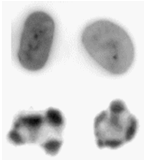

在开始使用流式细胞仪进行任何细胞凋亡研究之前,您应该尽可能首先通过目测确定这些细胞的存在,而不应依赖于各种流式细胞仪检测。凋亡细胞最初是通过其细胞核的特征性变化来识别的。这仍然是确认他们身份的最佳方法。通过用 DNA 染料染色和使用荧光显微镜可以观察到细胞核的变化(图 9.2)。

图 9.2。 正常(顶行)和凋亡 HL60(人早幼粒细胞系)细胞,用 PI 染色并通过共聚焦显微镜观察。